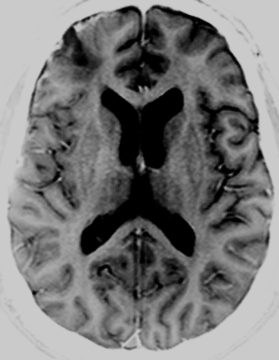

Pale-brain-2 1